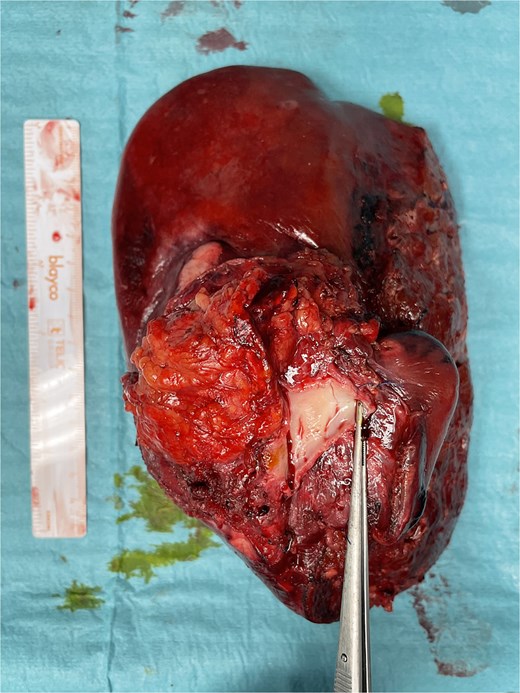

Vascular clamps were applied to the IVC. Before resection, we measured the expected vascular defect. An IVC defect measuring 5 cm in length and 2.5 to 3 cm in width was confirmed. The patch was tailored to 6 × 4 cm, allowing a repair larger than the defect to avoid tension and stenosis. We proceeded with resection of the IVC anterolateral wall. Reconstruction using the APFP, with the mesothelial side of the patch facing the lumen, was performed using a running 4–0 polypropylene suture (Fig. 4). It is essential to flush the vein with heparinized saline and avoid suture tension. Total IVC clamping time was 30 min. The video vignette demonstrates the surgical technique. The specimen is shown in Fig. 5.

Final specimen. The resected specimen shows intrahepatic cholangiocarcinoma with invasion of the IVC.